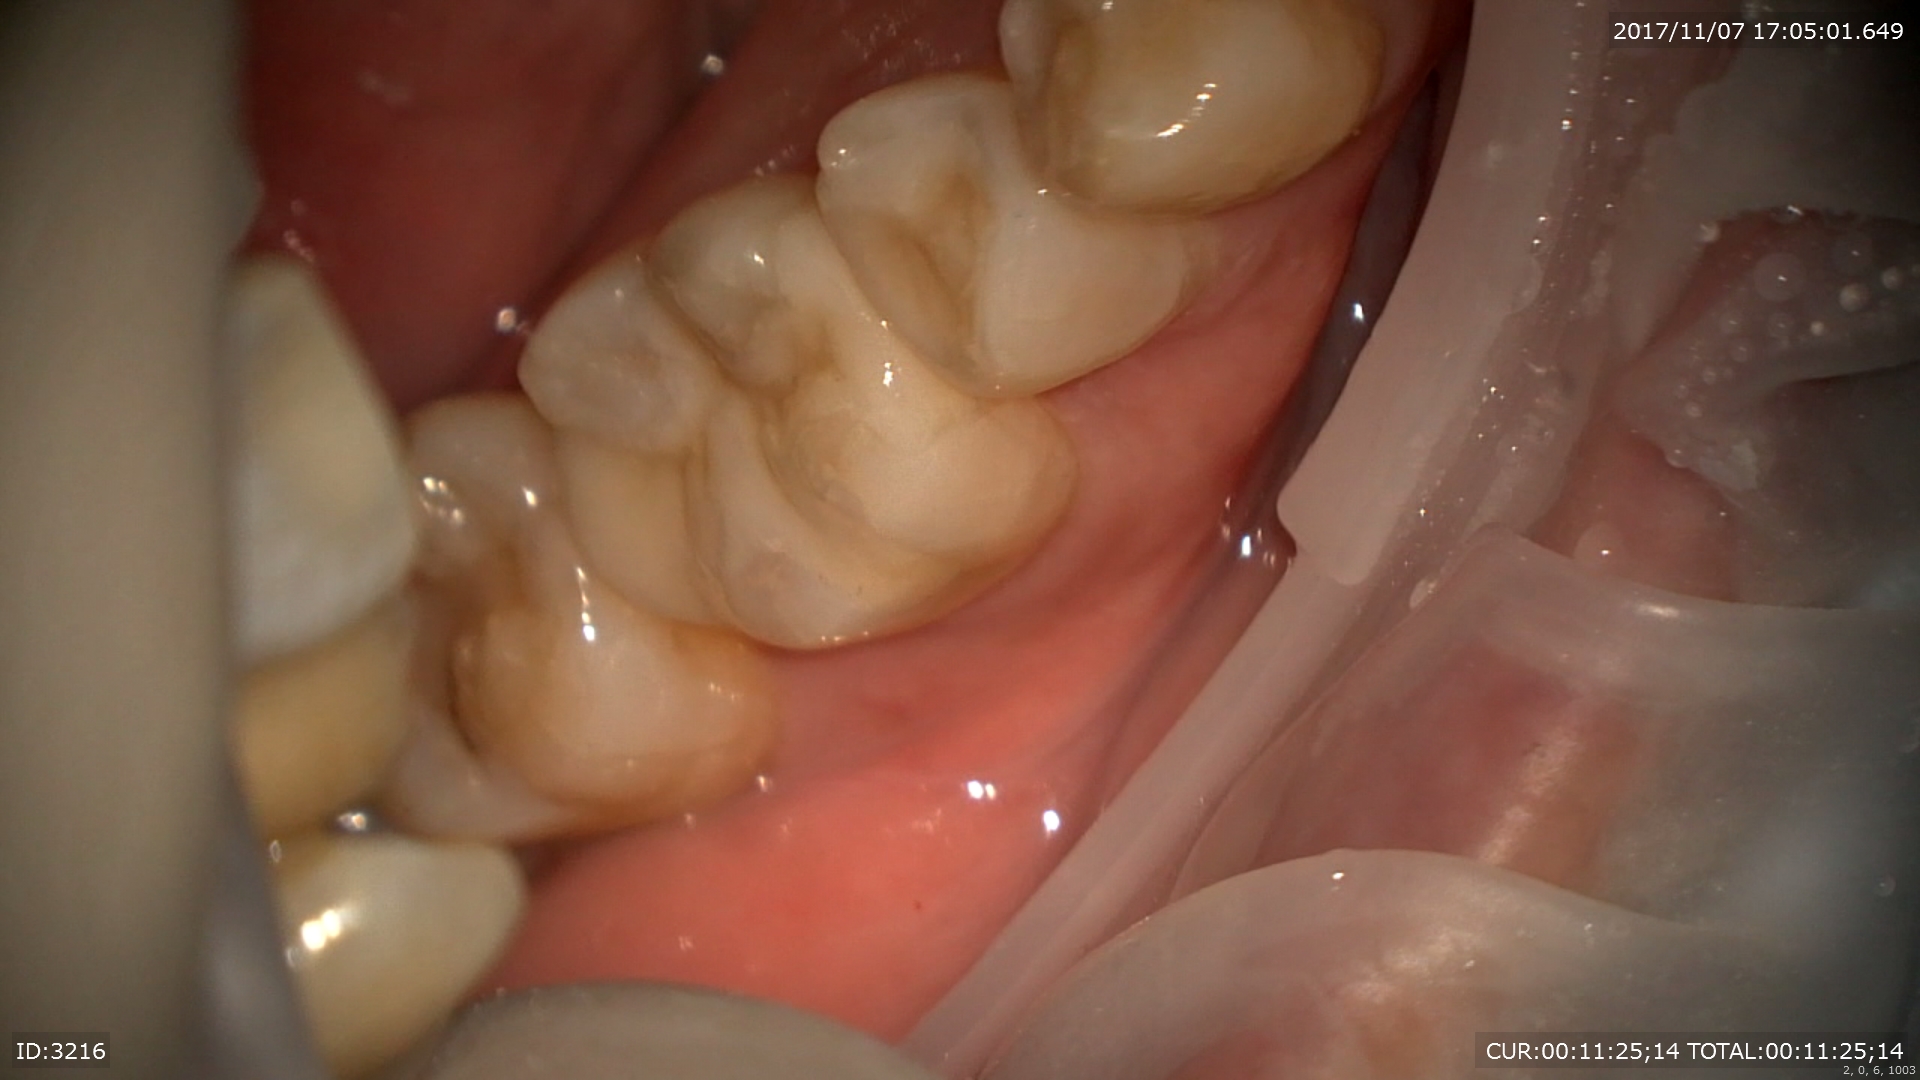

神経保護を行いました。

本日修復終了

このように当院ではむし歯治療においても術後までを考え治療を行っております。